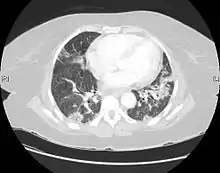

| CT scan of a patient with UIP. There is interstitial thickening, architectural distortion, honeycombing and bronchiectasis. | |

UIP may be diagnosed by a radiologist using computed tomography (CT) scan of the chest, or by a pathologist using tissue obtained by a lung biopsy.

Radiologically, the main feature required for a confident diagnosis of UIP is honeycomb change in the periphery and the lower portions (bases) of the lungs.[3]

On high-resolution computed tomography (HRCT), the following categories, depending on imaging findings, have been recommended by a collaborative effort by the American Thoracic Society, European Respiratory Society, Japanese Respiratory Society, and the Latin American Thoracic Society:[4]

- UIP pattern:[4]

- Honeycombing, with or without peripheral traction bronchiectasis; or bronchiolectasis (dilatation of the terminal bronchioles)[5]

- Predominantly subpleural and basal

- Often heterogenous distribution, being occasionally diffuse, and may be asymmetrical

There may be superimposed CT features such as mild ground-glass opacity, reticular pattern and pulmonary ossification.